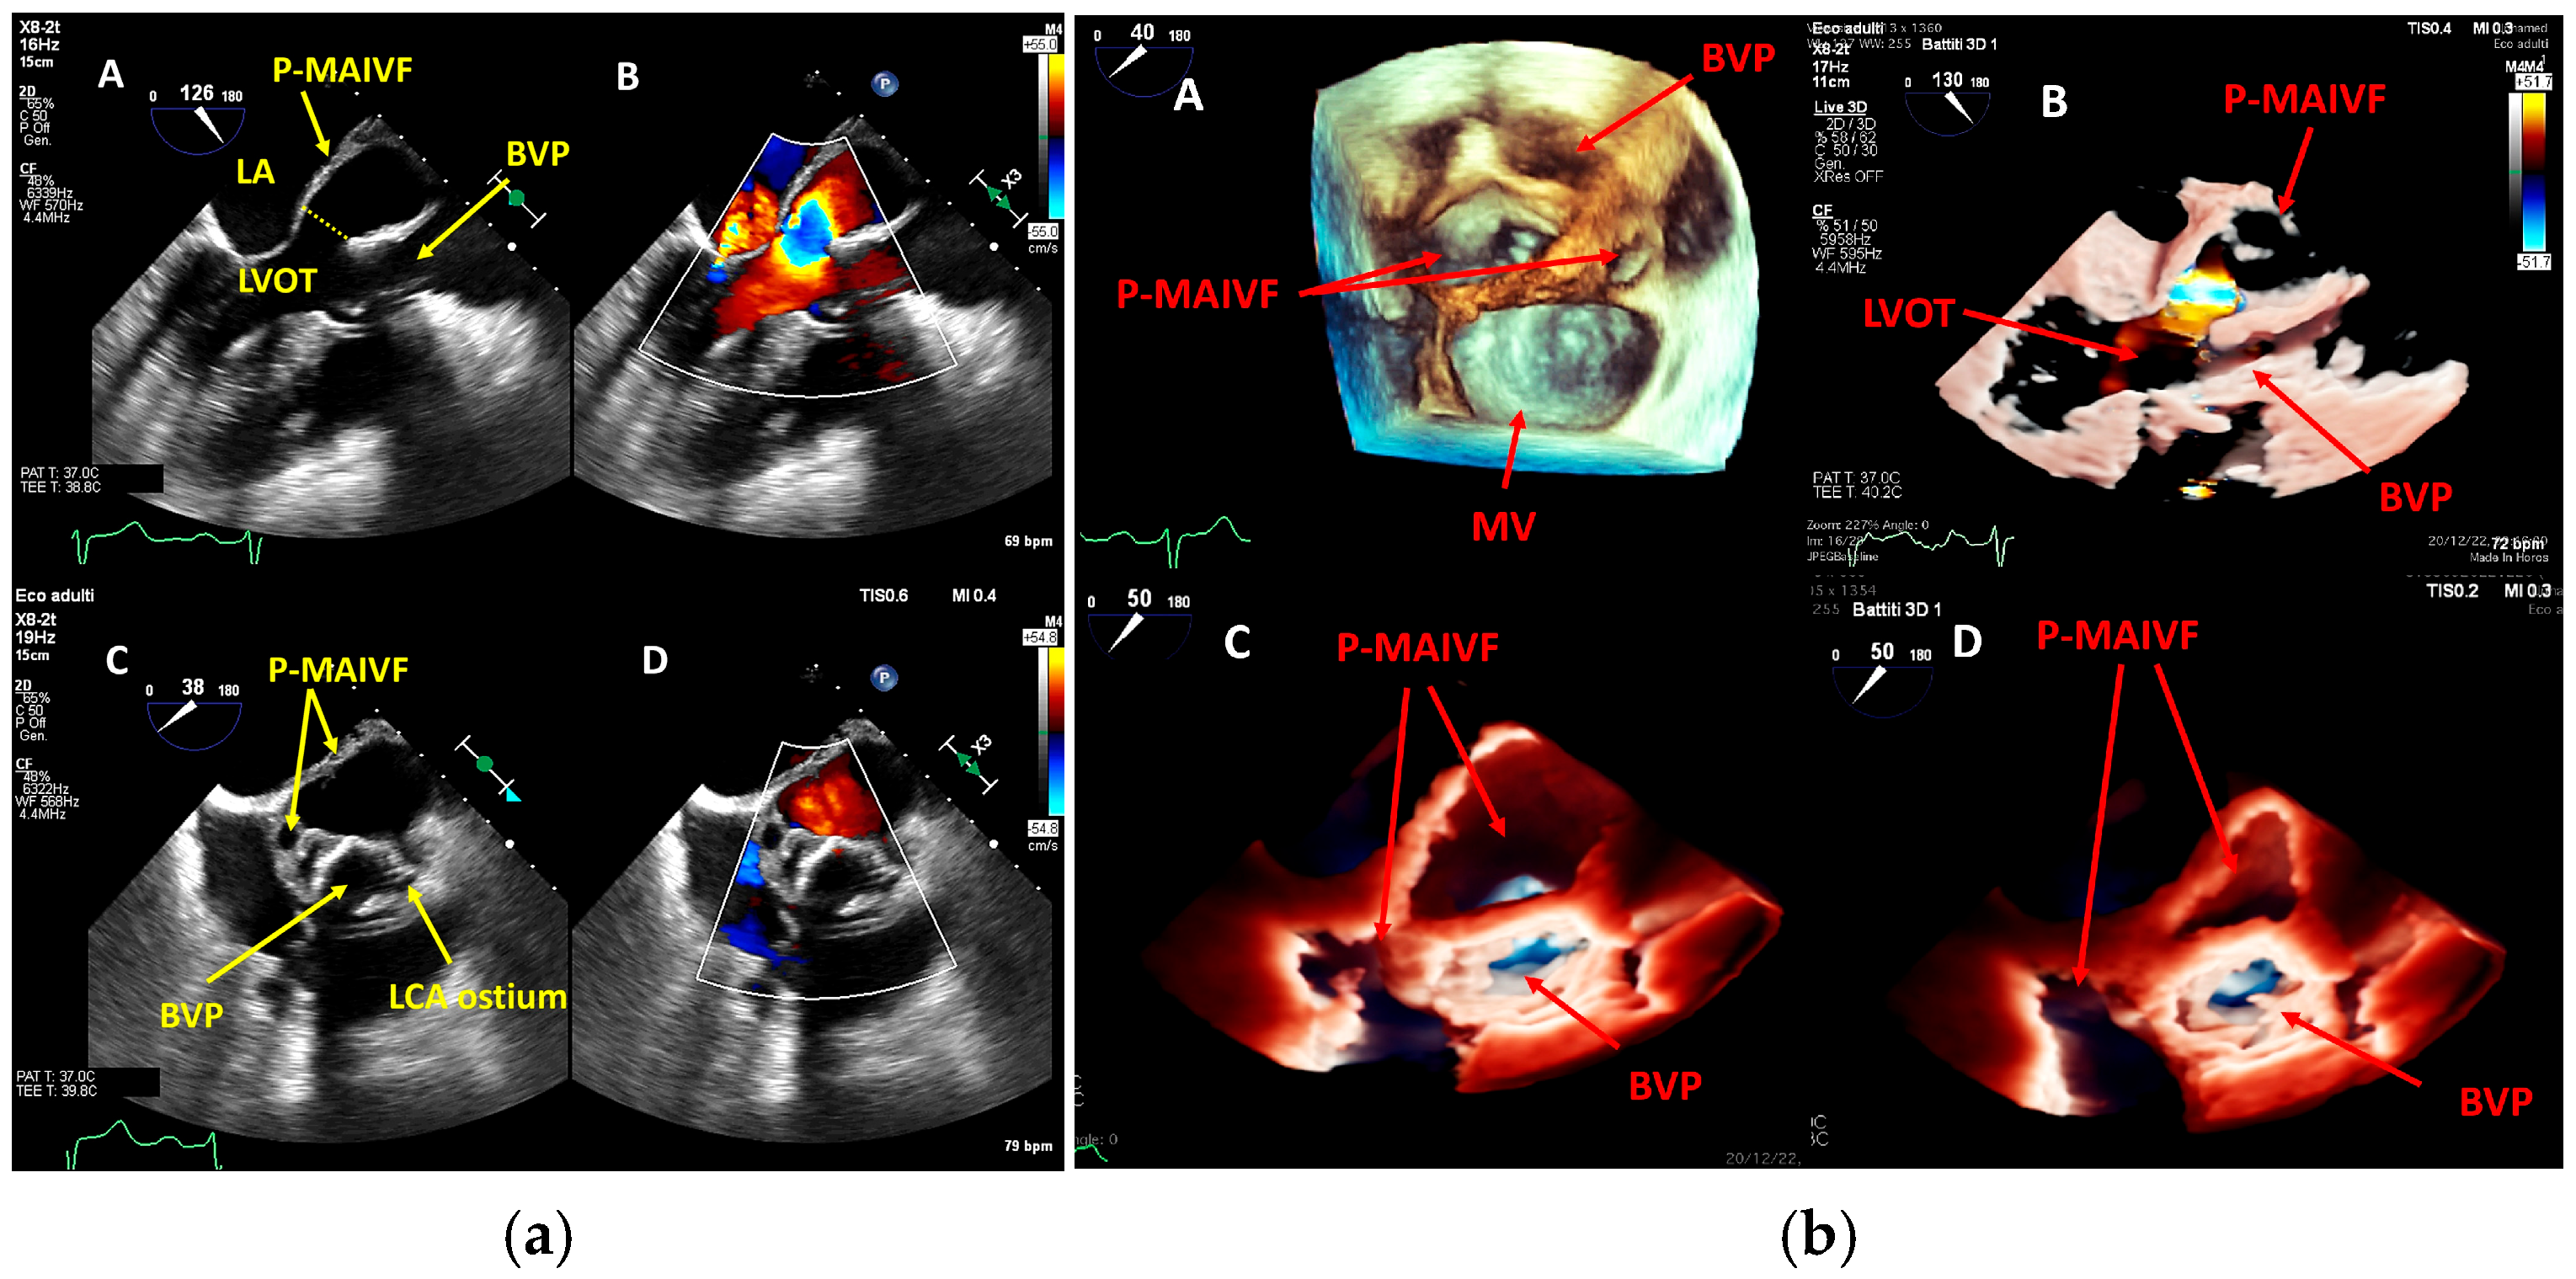

- perivalvular or perigraft abscess, an echolucent or echodense area adjacent to the valve annulus or prosthetic ring often with irregular borders and sometimes with evidence of cavity formation.

- pseudoaneurysm, a contrast-filled outpouching with a narrow neck communicating with the cardiac lumen, often adjacent to the valve annulus. On echocardiography, it appears as a pulsatile cavity with systolic expansion and diastolic collapse.

- intracardiac fistula, visualized as an abnormal communication between cardiac chambers or vessels, is often detected by using color Doppler.

| MAIVF | Mitral-Aortic Intervalvular Fibrosa |

| LCA | Left Coronary Artery |

| BVP | Biological Valve Prosthesis |

| LVOT | Left Ventricular Outflow Tract |

| LA | Left Atrium |